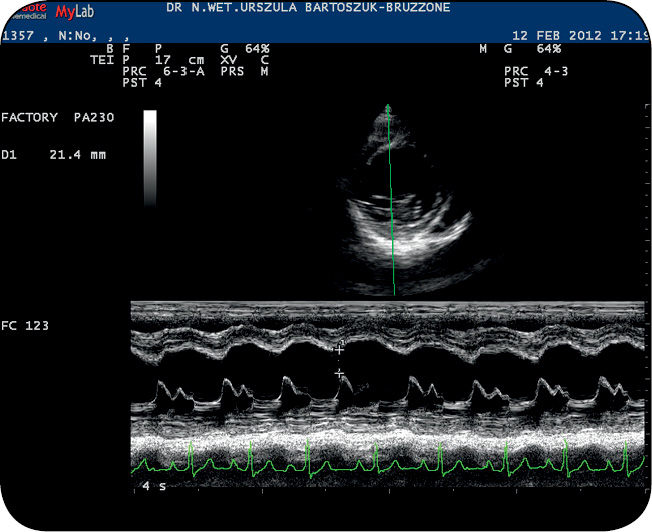

Przerost objętościowy lewej komory (niekiedy obu komór) ze znacznie ograniczoną czynnością skurczowo-rozkurczową jest zmianą najbardziej charakterystyczną dla kardiomiopatii rozstrzeniowej. W konsekwencji tych zmian notuje się również spadek frakcji skracania (FS), spadek frakcji wyrzutowej (EF) i wzrost odległości EPSS. Ten ostatni parametr zależny jest w dużym stopniu od ograniczenia funkcji diastolicznych komory – im funkcje te są bardziej upośledzone, tym większą wartość osiąga EPSS. U wielu pacjentów można również potwierdzić ujemną korelację pomiędzy wartościami EPSS a EF (1).

Wartość EPSS > 9 mm uważa się za podwyższoną (ryc. 1). Narastająca rozstrzeń lewej komory prowadzi do zmiany jej geometrii – staje się ona bardziej kulista, przez co rośnie indeks sferyczności (ryc. 2). Wraz z postępującą niewydolnością funkcjonalną mięśniówki lewej komory (lub obu komór) dochodzi do przerostu objętościowego lewego przedsionka (lub obu przedsionków), a także do wtórnej niedomykalności i przepływu zwrotnego mitralnego (lub mitralnego i trójdzielnego). W przebiegu kardiomiopatii rozstrzeniowej zawsze dochodzi do zaburzeń parametrów funkcjonalnych (skurczowych i rozkurczowych) lewej komory (1, 4).